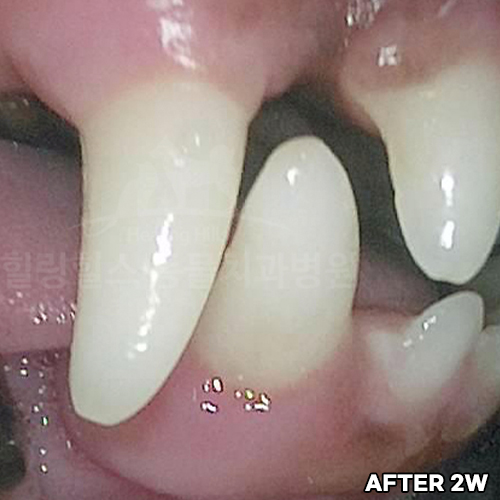

[강아지 치아의 구멍 레진치료 후 2주 경과]